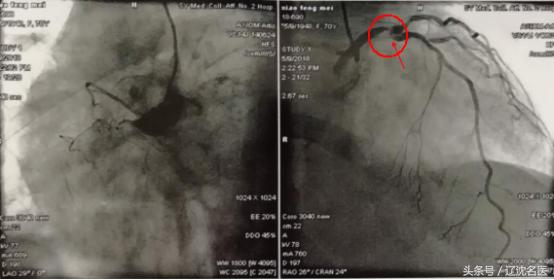

马晶茹主任对其病情做了缜密的分析和评估,决定为患者进行冠脉造影检查,结果显示正常人的三支冠状动脉中她有两支血管完全闭塞,仅留有前降支,但左主干末端99%狭窄,前降支开口80%狭窄。

就是这头发丝般的缝隙,入前降支开口不到2cm处的前后两端,连续两个直角弯。这是及其危重的一种血管病变,患者病情及心肺功能无法实施冠状动脉旁路移植术,而介入医生面对这种无保护的左主干病变,又有两个极难操控的高度狭窄及又非常近距离的两个直角弯,再加上患者的心功能不能耐受稍长时间的手术,所以如果做,下不来台的风险可想而知;如果不做,她能存活下来的可能也是微乎其微。

术前